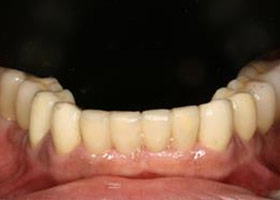

3. 經過一年多牙周病治療與人工植牙重建病患恢復了完整的牙齒。

proimages/case/Artificial_implant/all-3.jpg